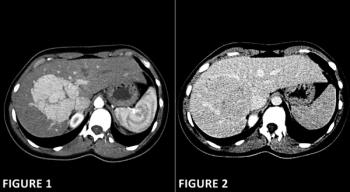

A 50-year-old man undergoes CT examination for workup of hematuria and abdominal pain. Noncontrast and postcontrast images from the CT are shown. What is your diagnosis?